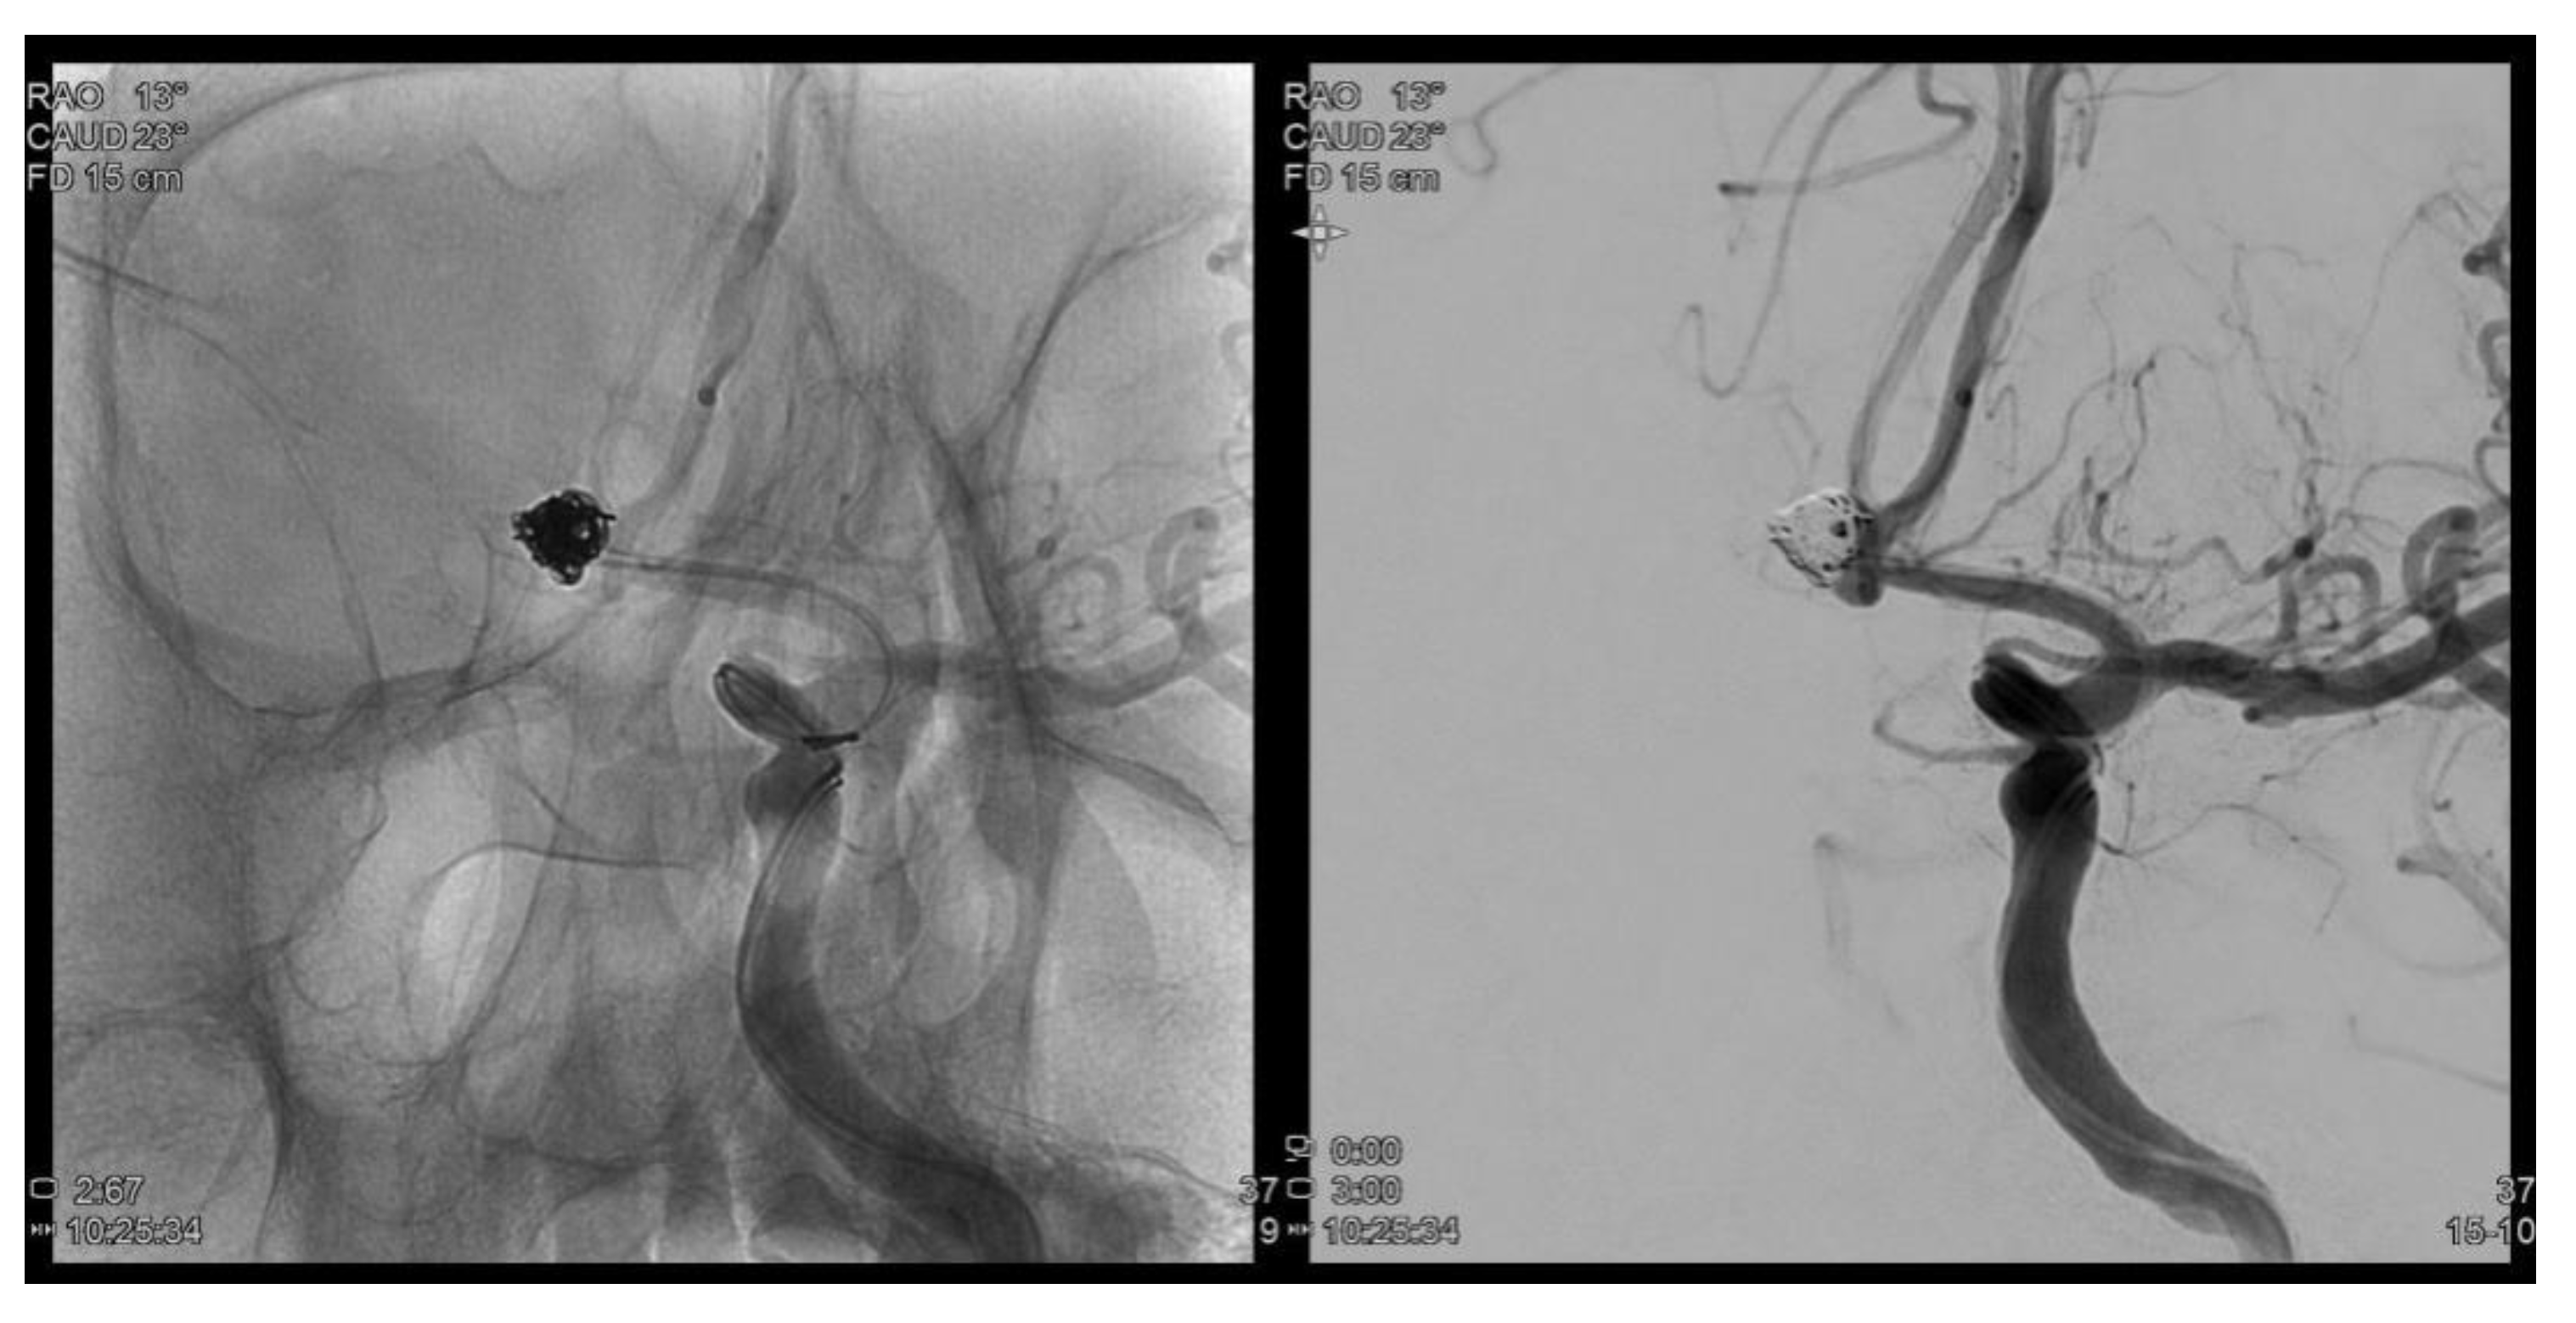

Figure 1.

Trans femoral cerebral angiography images show a 6.2 mm sized AcomA (anterior communiating artery) aneurysm and AcomA aneurysm was embolized following coil procedure.